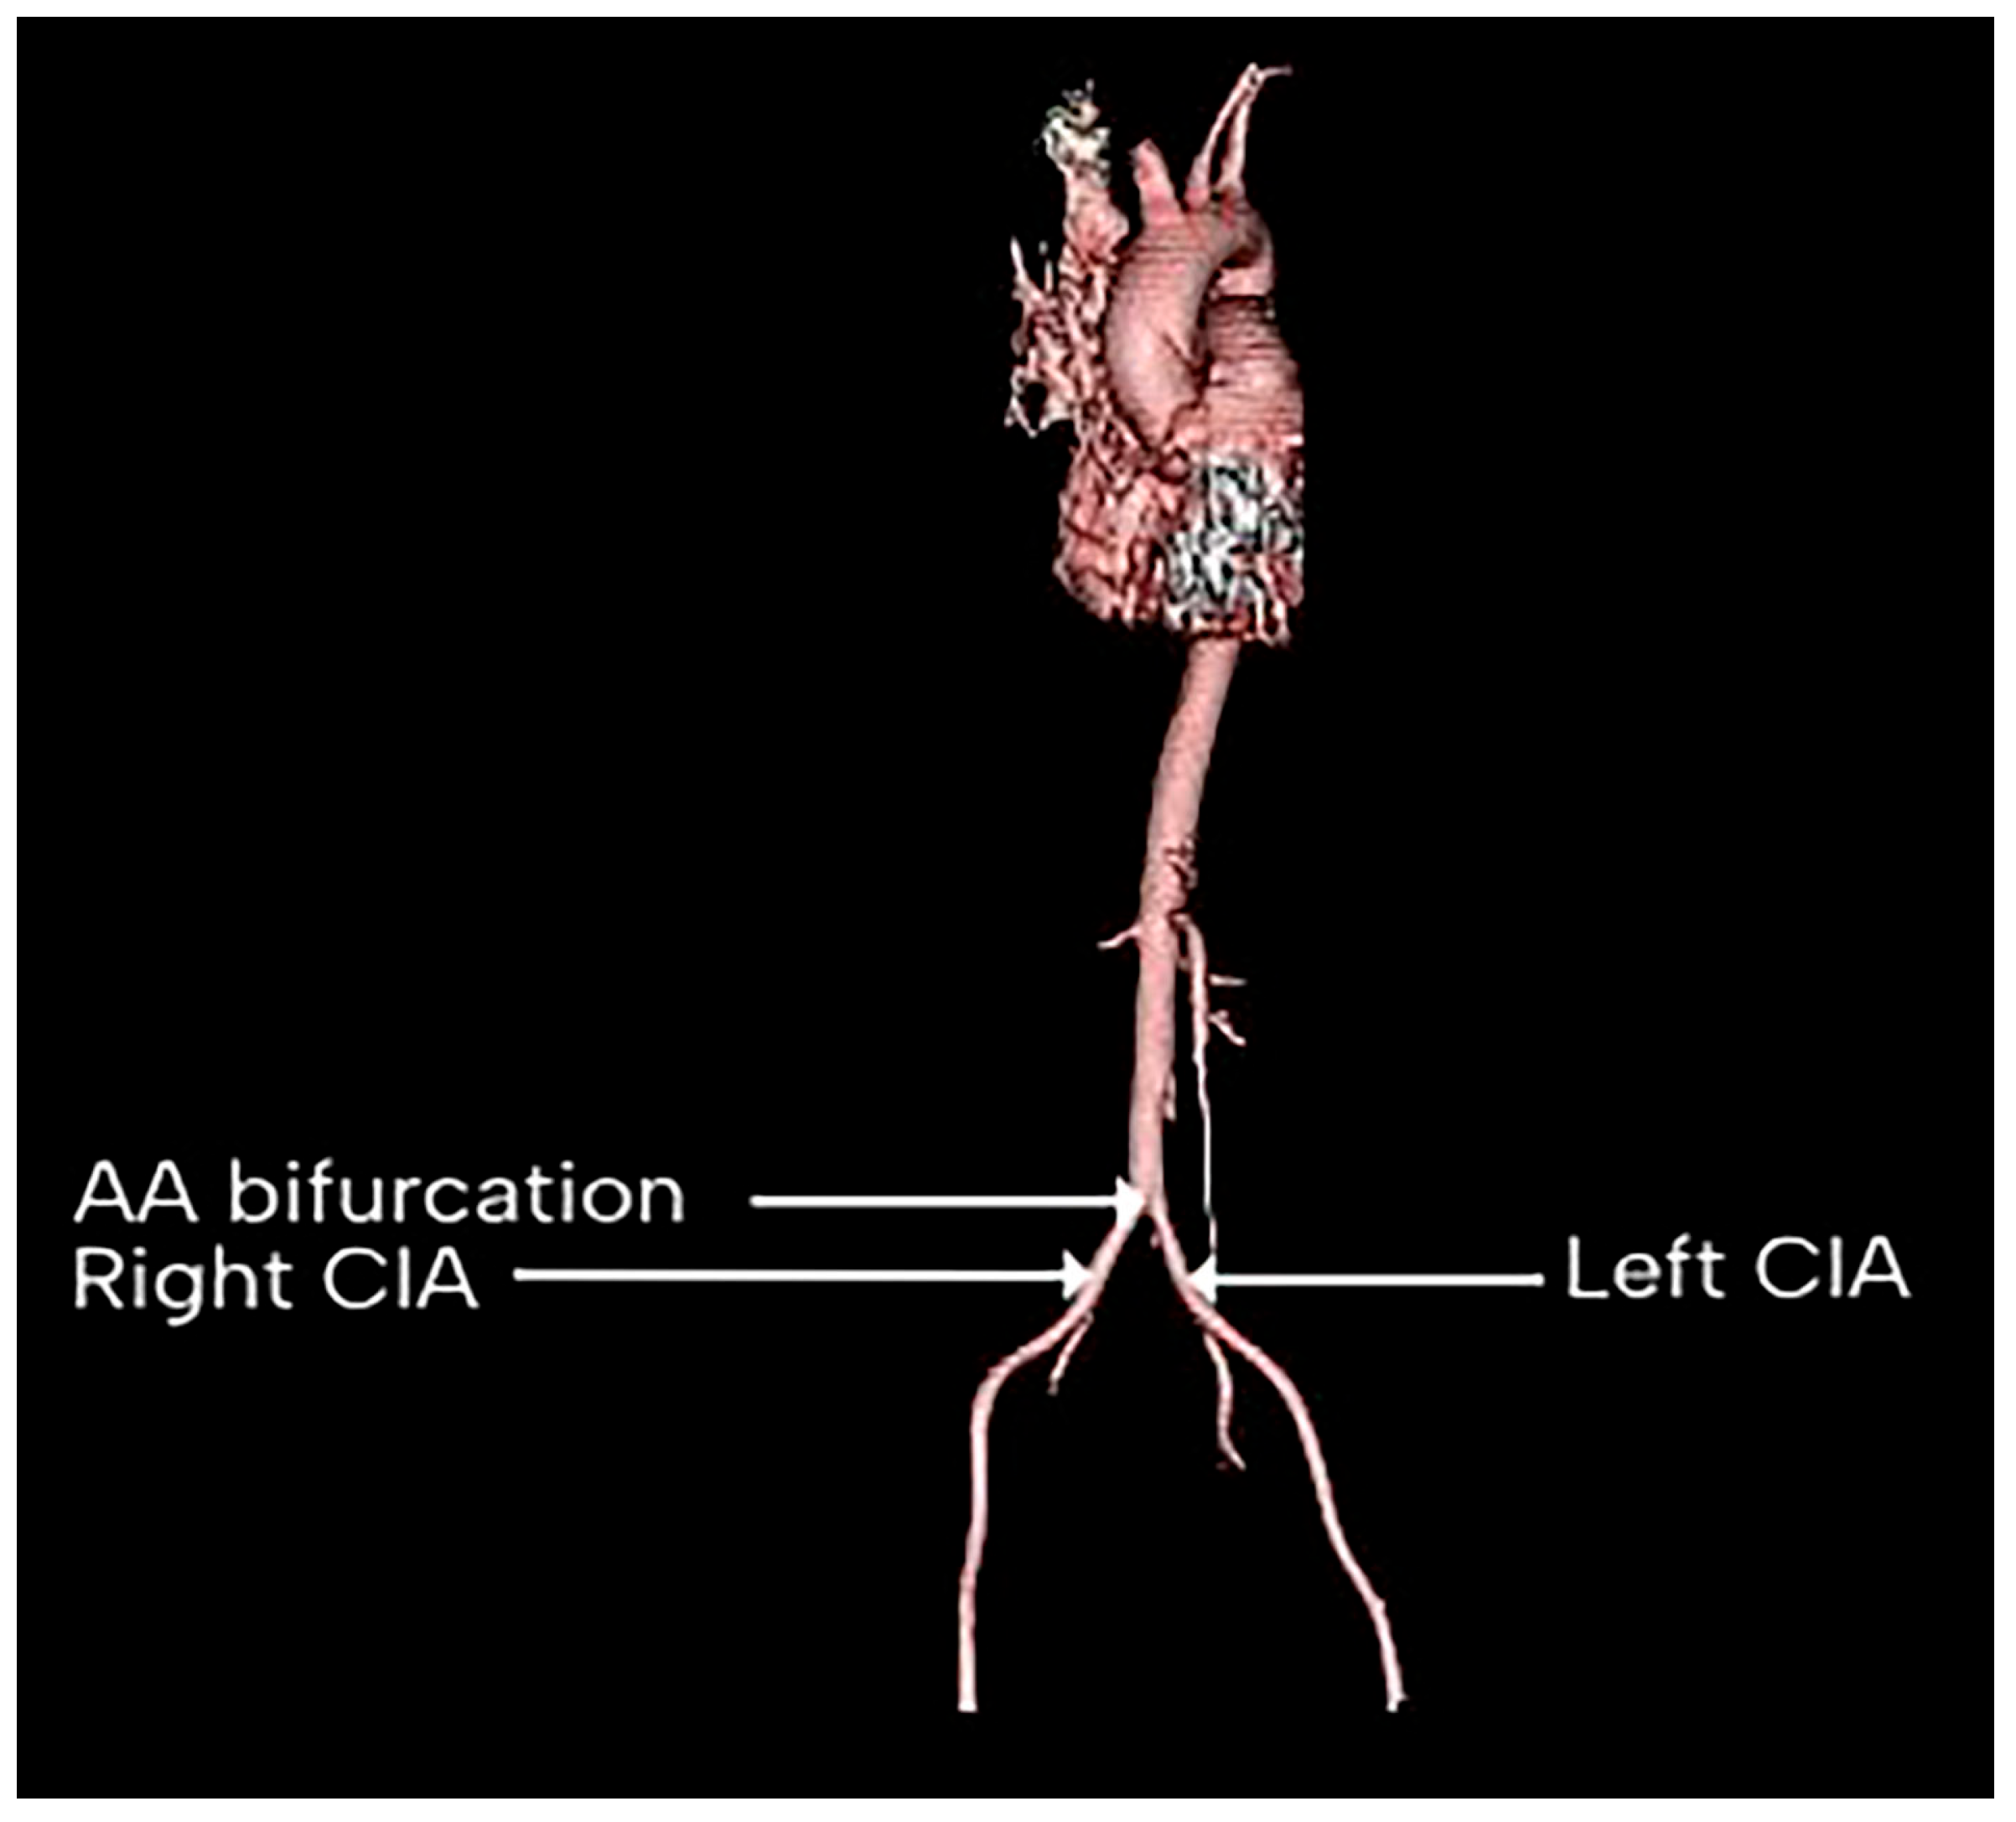

Level of Abdominal Aorta Bifurcation and Its Relation to the Ureter: A Radiological Study with Clinical Implications

3. Results